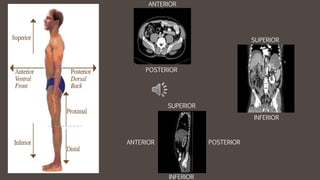

ANTERIOR

POSTERIOR

SUPERIOR

INFERIOR

Sagittal

plane

divides the

body into

right and

left

portions.

This is a

vertical

Coronal

plane divides

the body into

front and

back or

anterior and

plane.

Axial plane

and inferior

horizontal